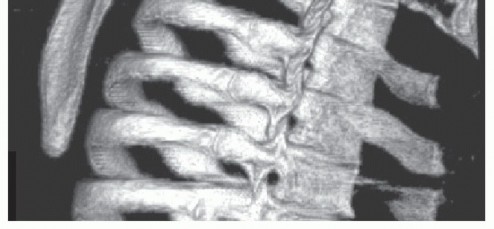

Computed Tomography (CT) with 3D volumetric reconstruction is the gold standard for evaluating the osseous morphology of the superomedial angle. It precisely delineates the anterior curvature of the scapula, identifies osteochondromas, and assesses thoracic cage congruency.

Typically, a triangular wedge of bone measuring 2 to 3 cm at its base is resected. The levator scapulae insertion at the superomedial angle is partially detached during this process. The resection is carried down to bleeding cancellous bone, ensuring a smooth, contoured surface that will no longer abut the thoracic cage during scapular excursion. Fluoroscopy may be utilized intraoperatively to confirm the adequacy of the osseous resection.

An arthroscopic acromionizer or high-speed motorized burr is introduced. The resection targets the prominent superomedial angle, aiming to remove the bony impingement while preserving the structural integrity of the scapular spine.